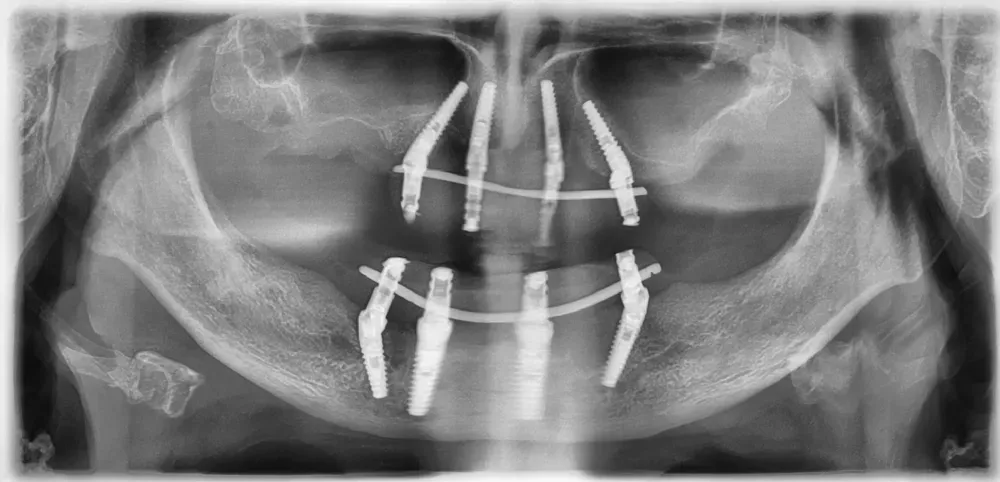

Le immagini radiografiche che seguono testimoniano alcune delle tante soluzioni tecniche che ho utilizzato per le arcate a carico immediato nel corso della mia carriera. Ogni caso presenta sfide diverse e richiede un approccio personalizzato.

Anche nei pazienti anziani con protesi mobili (dentiere) che presentano condizioni critiche dal punto di vista osseo, gli interventi di implantologia a carico immediato possono essere portati a termine con successo.

Tutto dipende dalle condizioni di salute generale e dall’anatomia residua. Non esiste un limite di età assoluto, ma solo una valutazione attenta del rapporto rischio-beneficio per ogni singolo paziente.